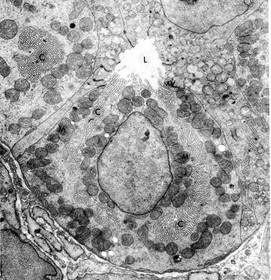

TEM OF Pancreatic acinar cell

A : Lumen B : Zymogen granules C : Nucleus With evident nucleolus D : rER